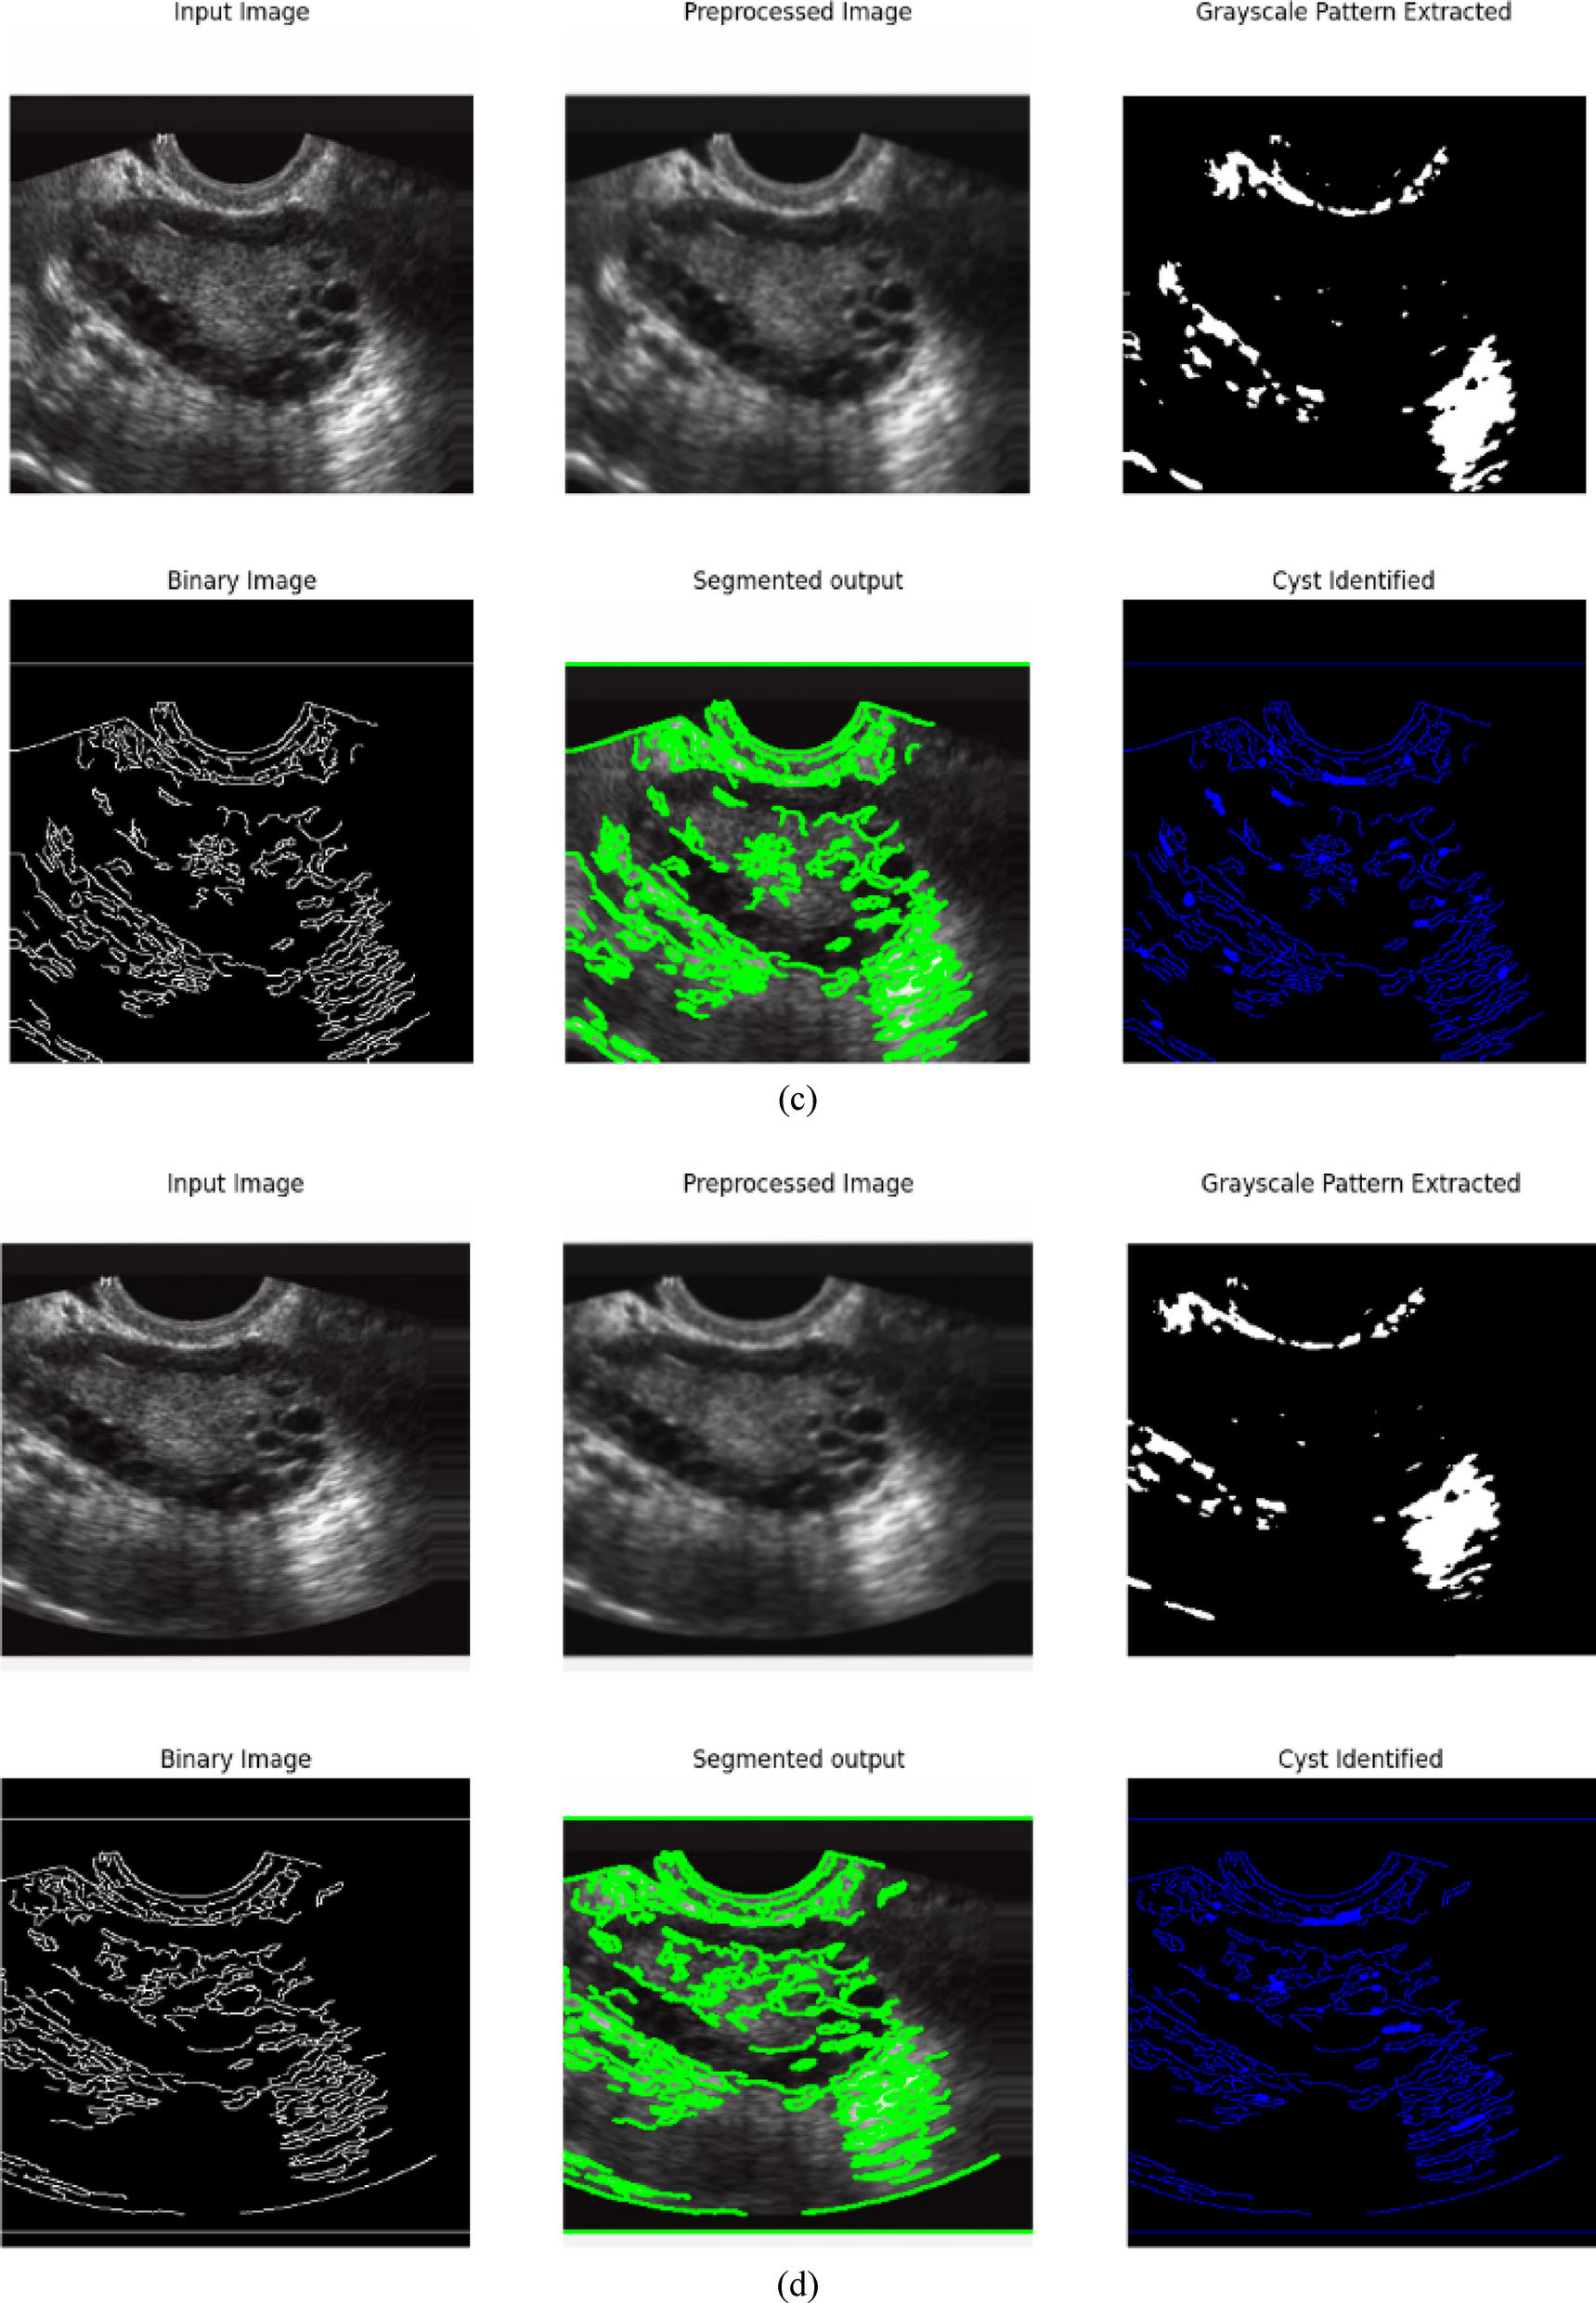

From: Advanced holographic convolutional dense networks and Tangent runner optimization for enhanced polycystic ovarian disease classification

Sample input and output images of Kaggle PCOD image dataset.